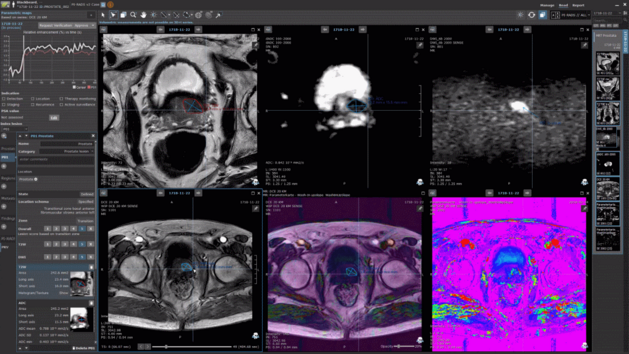

At this year’s RSNA, Mint Medical presented its AI approach to the audience at the AI theater. Tobias Gottmann and Aditya Jayaram highlighted how…

At this year’s RSNA, Mint Medical presented its AI approach to the audience at the AI theater. Tobias Gottmann and Aditya Jayaram highlighted how…